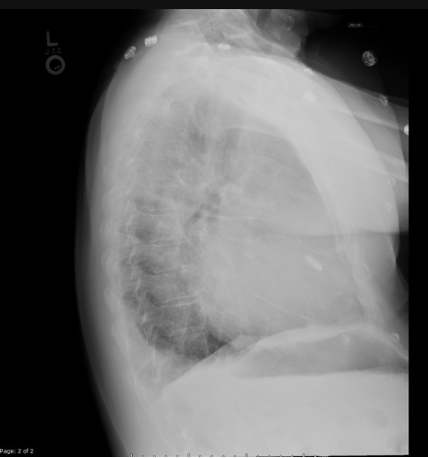

Complication after Nissen fundoplication with this postop barium swallow and EGD view looking at the hiatus

What is a slipped wrap?